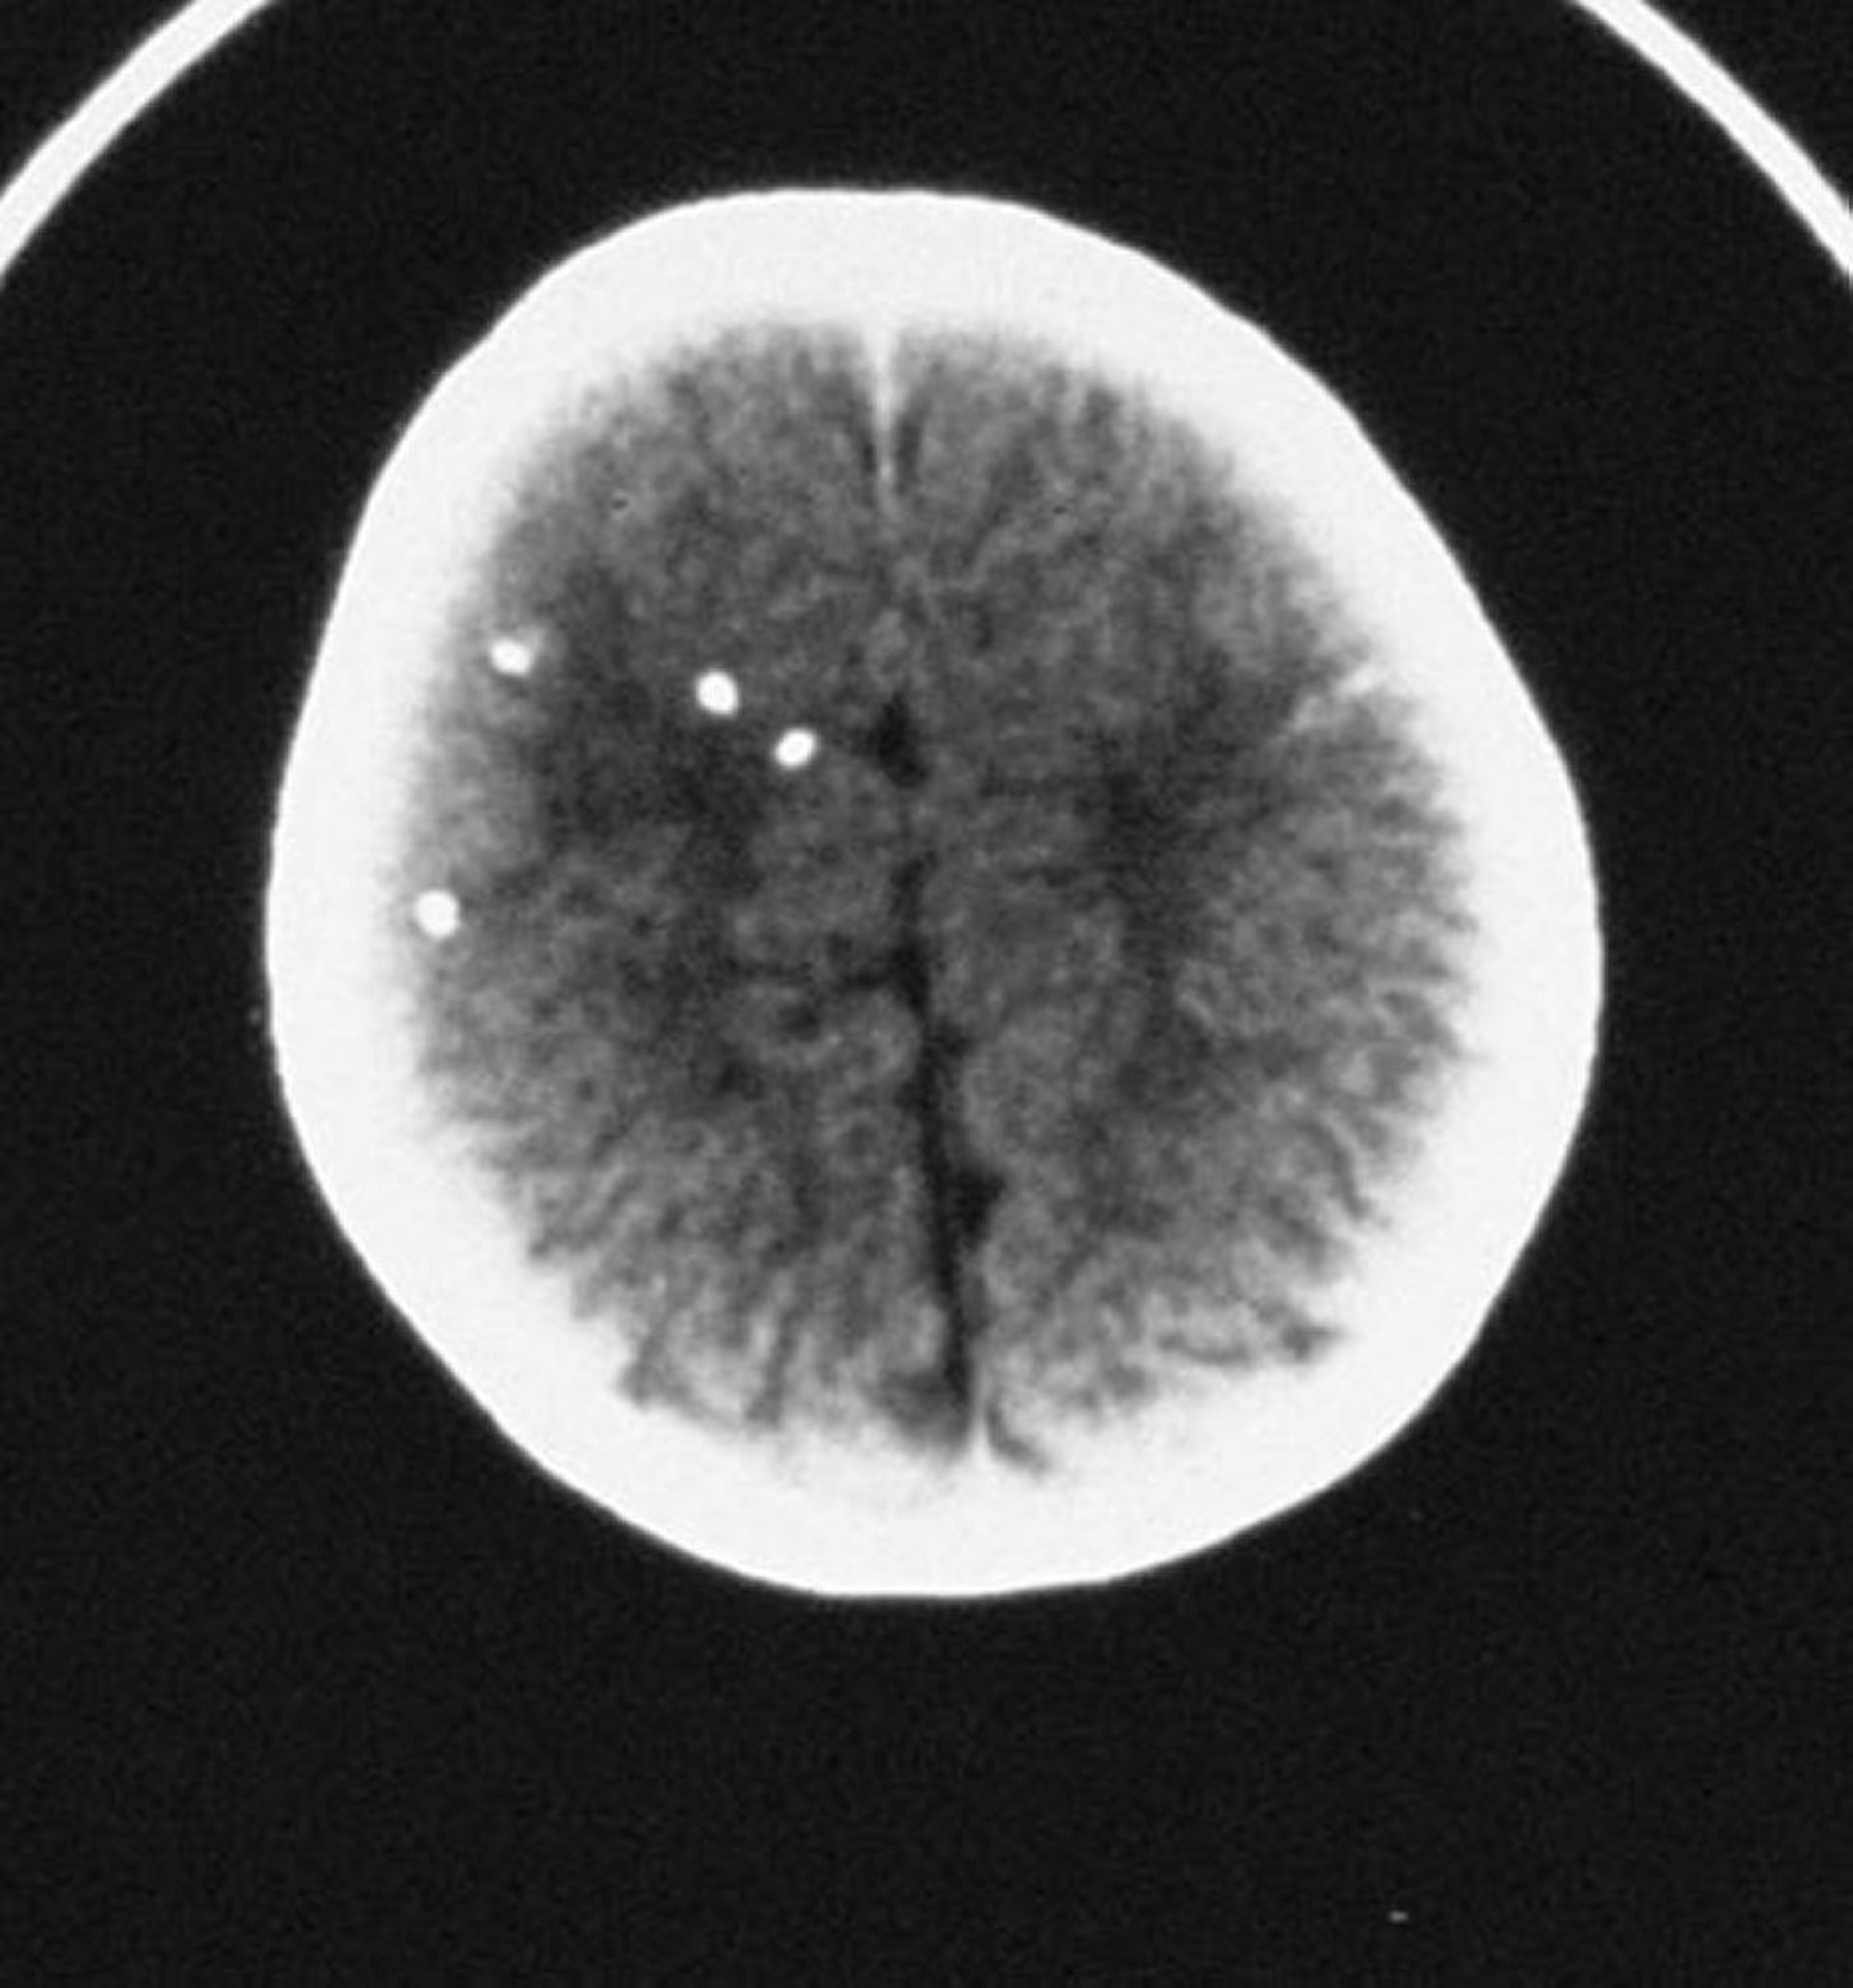

Toxoplasmosis congénita

Esta tomografía computarizada muestra calcificaciones intracraneales dispersas.